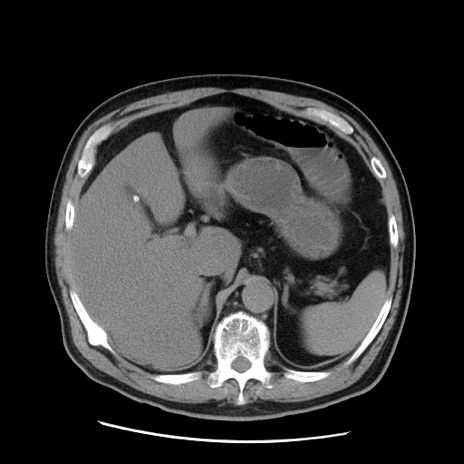

症例20(横断像)

【症例】 60歳代男性

【主訴】 腹部膨満、嘔吐

【現病歴】5日前頃より倦怠感を認め食事量減少し4日前の朝嘔吐、食事摂取困難となった。 3日前近医受診し点滴施行され整腸剤などを処方された。 当日他院を受診し、腹部膨満著明、炎症反応の上昇(CRP10.8、WBC11200)あり、紹介受診となる。

【身体所見】 意識JCS1 受け答えがはっきりしないBP 111/57mHg、 P 67bpm、、BT35.2°C、SpO2 97%(RA)、 腹部:膨隆、打診で鼓音あり、全体的に圧痛有り、腸蠕動音(-)、反跳痛ははっきりせず。

【データ】WBC 11400、CRP 14.20